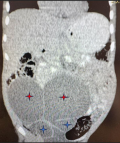

Diagnostic assessment: laboratory investigation shows normal full blood count and renal function, as well as sterile urine cultures. The abdominal CT scan shown in Figure 3 shows Grade 4 hydronephrosis with severe hydroureters of the right and Grade 2 hydronephrosis on the left.

Figure 3: abdominopelvic CT scan showing bilateral hydroureteronephrosis; the red stars show bilateral hydronephrosis, and the blue stars show the bilateral hydroureters